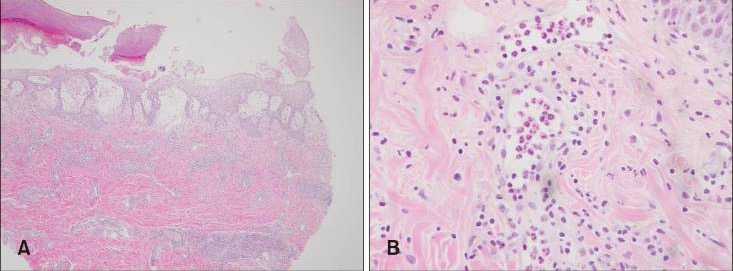

图片患者皮疹形态

图片来源:PubMed [2]